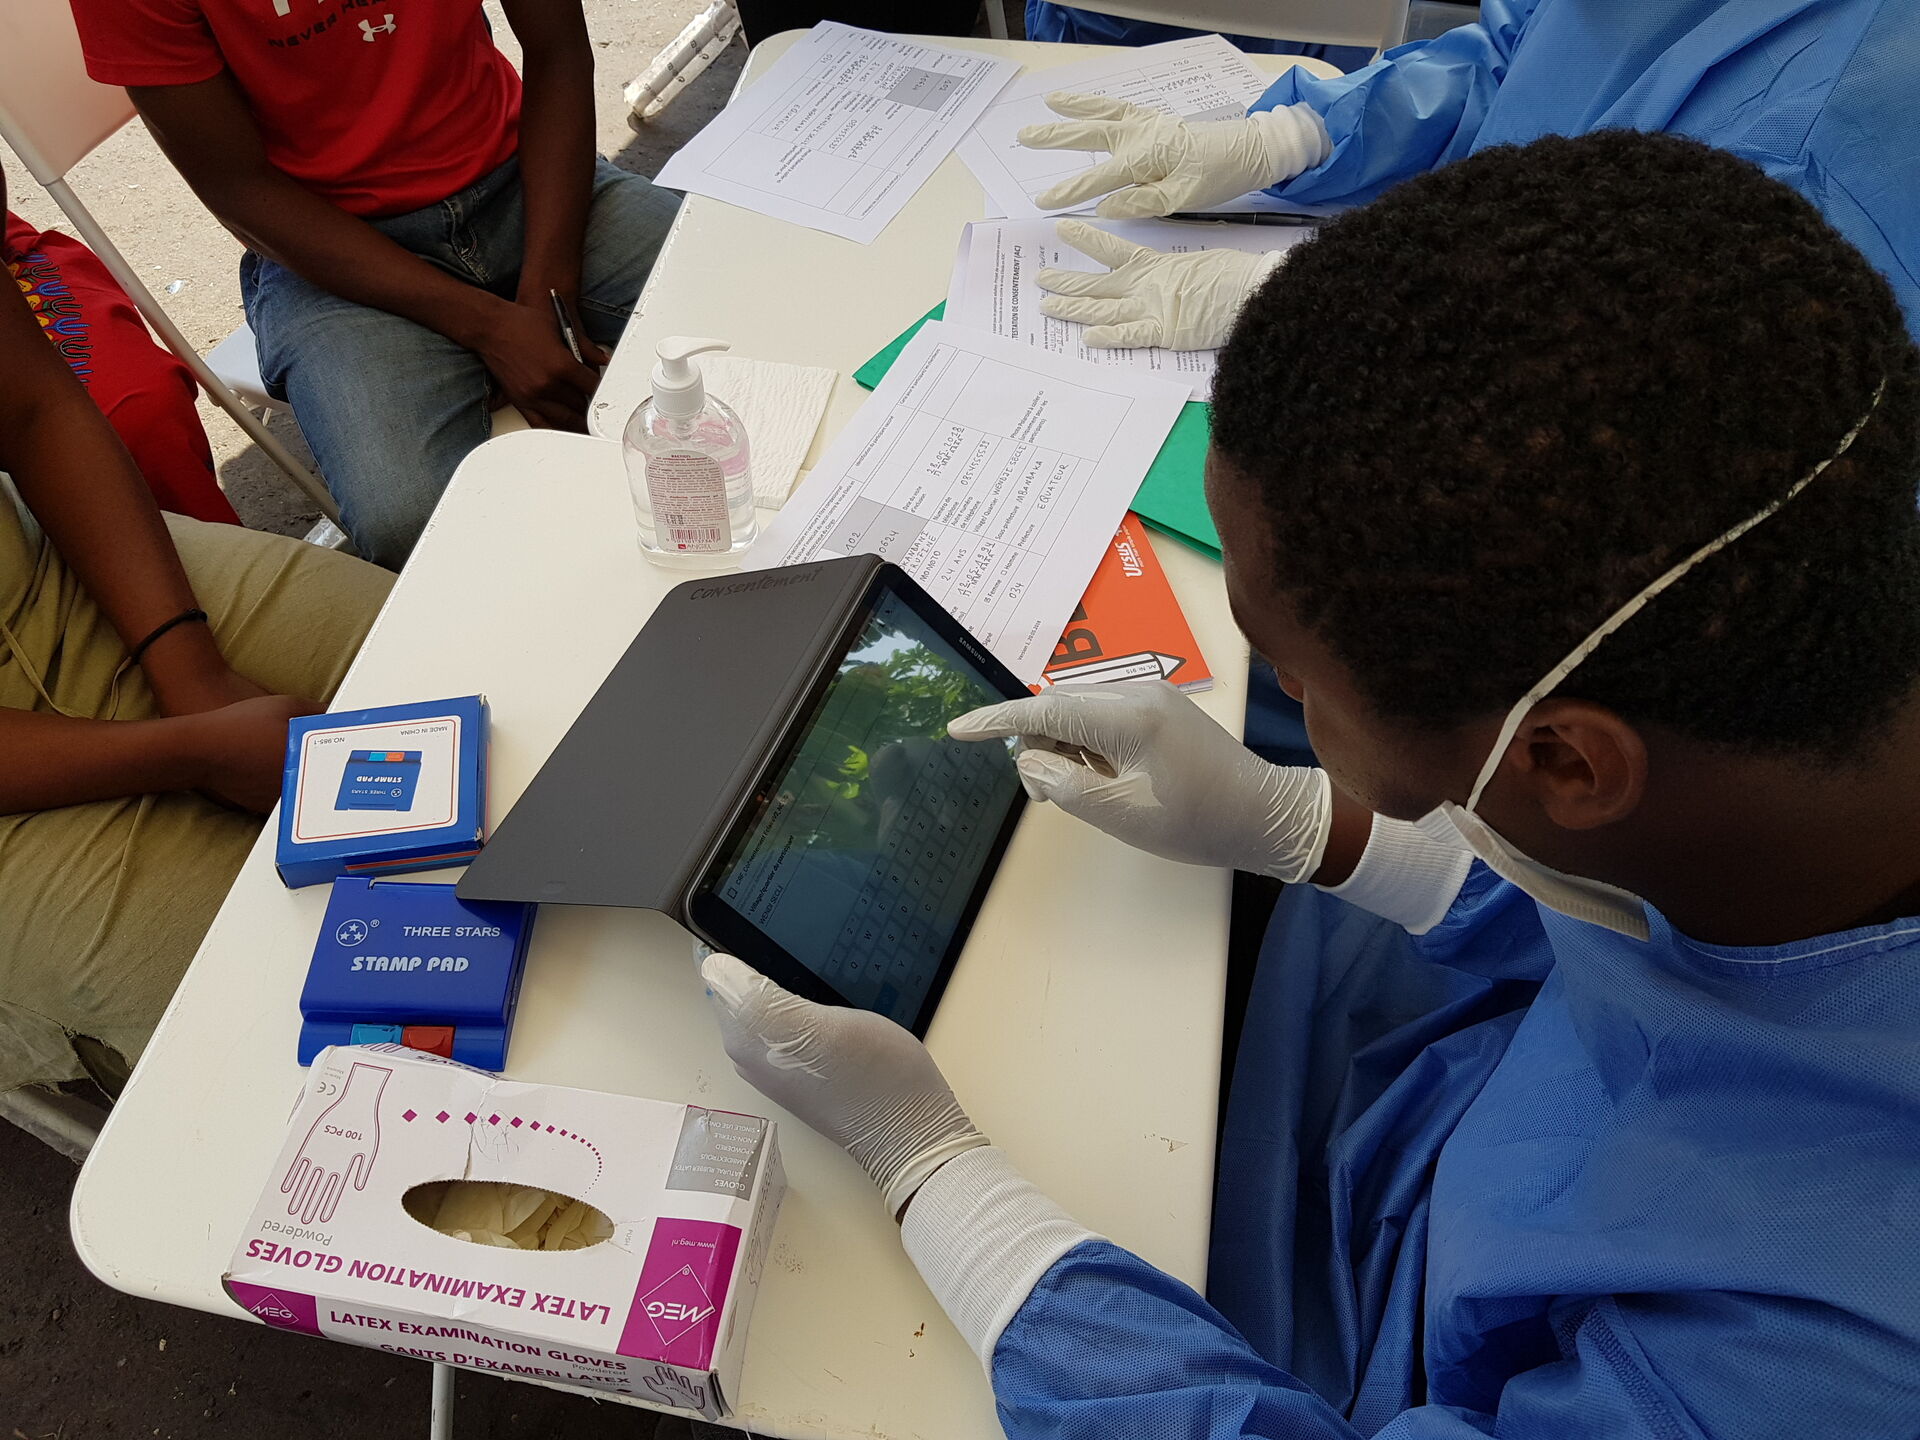

All →Ebola outbreak in Africa

Ebola preparedness and response plan